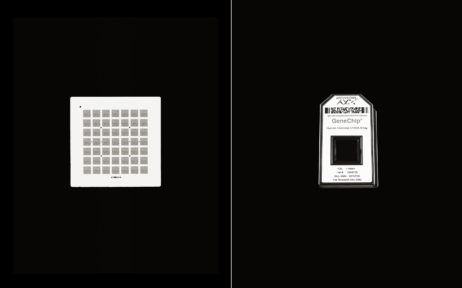

Affymetrix _ "History Of The Gene Chip"

Affymetrix _ "History Of The Gene Chip"

Affymetrix _ "History Of The Gene Chip"